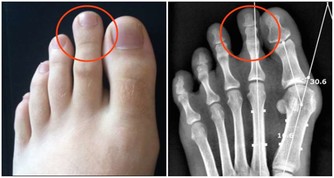

2、牙齒和舌頭老碰撞

很多原因會造成牙齒和舌頭異常接觸,但如果牙齒和舌頭經常碰撞,

在長期碰觸磨損中可能使得舌頭經常出現傷口,成為引發舌癌的病因。